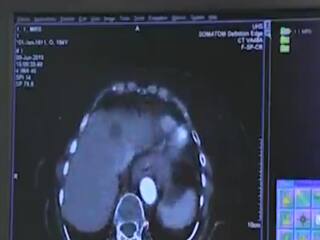

હાઇરિઝોલ્યુશન કમ્પ્યૂટર ટોમોગ્રાફી (HRCT) ને કોરોનાનો ટેસ્ટ માનતા લોકોએ ચેતવાની જરૂર છે. સિવિલના રેડિયોલોજી વિભાગના ડો. પંકજ અમીન જણાવે છે કે, એચઆરસીટીમાં વ્યક્તિની છાતીએ 1 હજાર એક્સ-રે જેટલું રેડિએશન ઝીલવું પડે છે માટે ડોક્ટરની સલાહ વગર આ ટેસ્ટ કરાવવો જોઈએ નહીં.કારણ કે HRCT સ્કેન વાસ્તવમાં કોરોનાનો ટેસ્ટ જ નથી. રેડિયો ડાયોગ્નોસીસમાં HRCT સ્કેનનો ઉપયોગ વાઈરસની અસર જોવા કરાય છે.આ ટેસ્ટ કરાવવો જોઈએ પરંતું આ ટેસ્ટ માટેનો ચોક્કસ તબક્કા હોય છે. કોરોનાની શરૂઆતમાં જ આ ટેસ્ટ કરાવવો સલાહભર્યો નથી. આ ટેસ્ટ 10-15 સેકન્ડમાં રિપોર્ટ આપે છે. કોરોના પ્રારંભિક તબક્કામાં હોય તો આ ટેસ્ટથી ડિટેક્ટ થતો નથી. જેથી 5-7 દિવસ પછી ફરી ટેસ્ટ કરવો પડે છે.